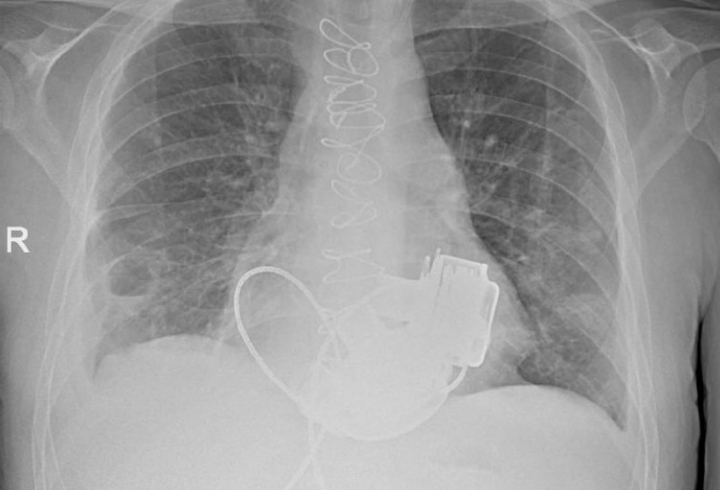

Уникальный пациент, которому впервые в РФ имплантировали сразу два искусственных желудочка сердца, готовится к выписке из Мариинской больницы, сообщает пресс-служба комитета по здравоохранению Петербурга.

«В конце ноября 2025 года ему впервые в России имплантировали сразу два искусственных желудочка сердца - левое и правое», - рассказали в ведомстве.

Сложнейшая операция продолжалась порядка четырех часов. Самым трудным было синхронизировать работу двух искусственных желудочков.